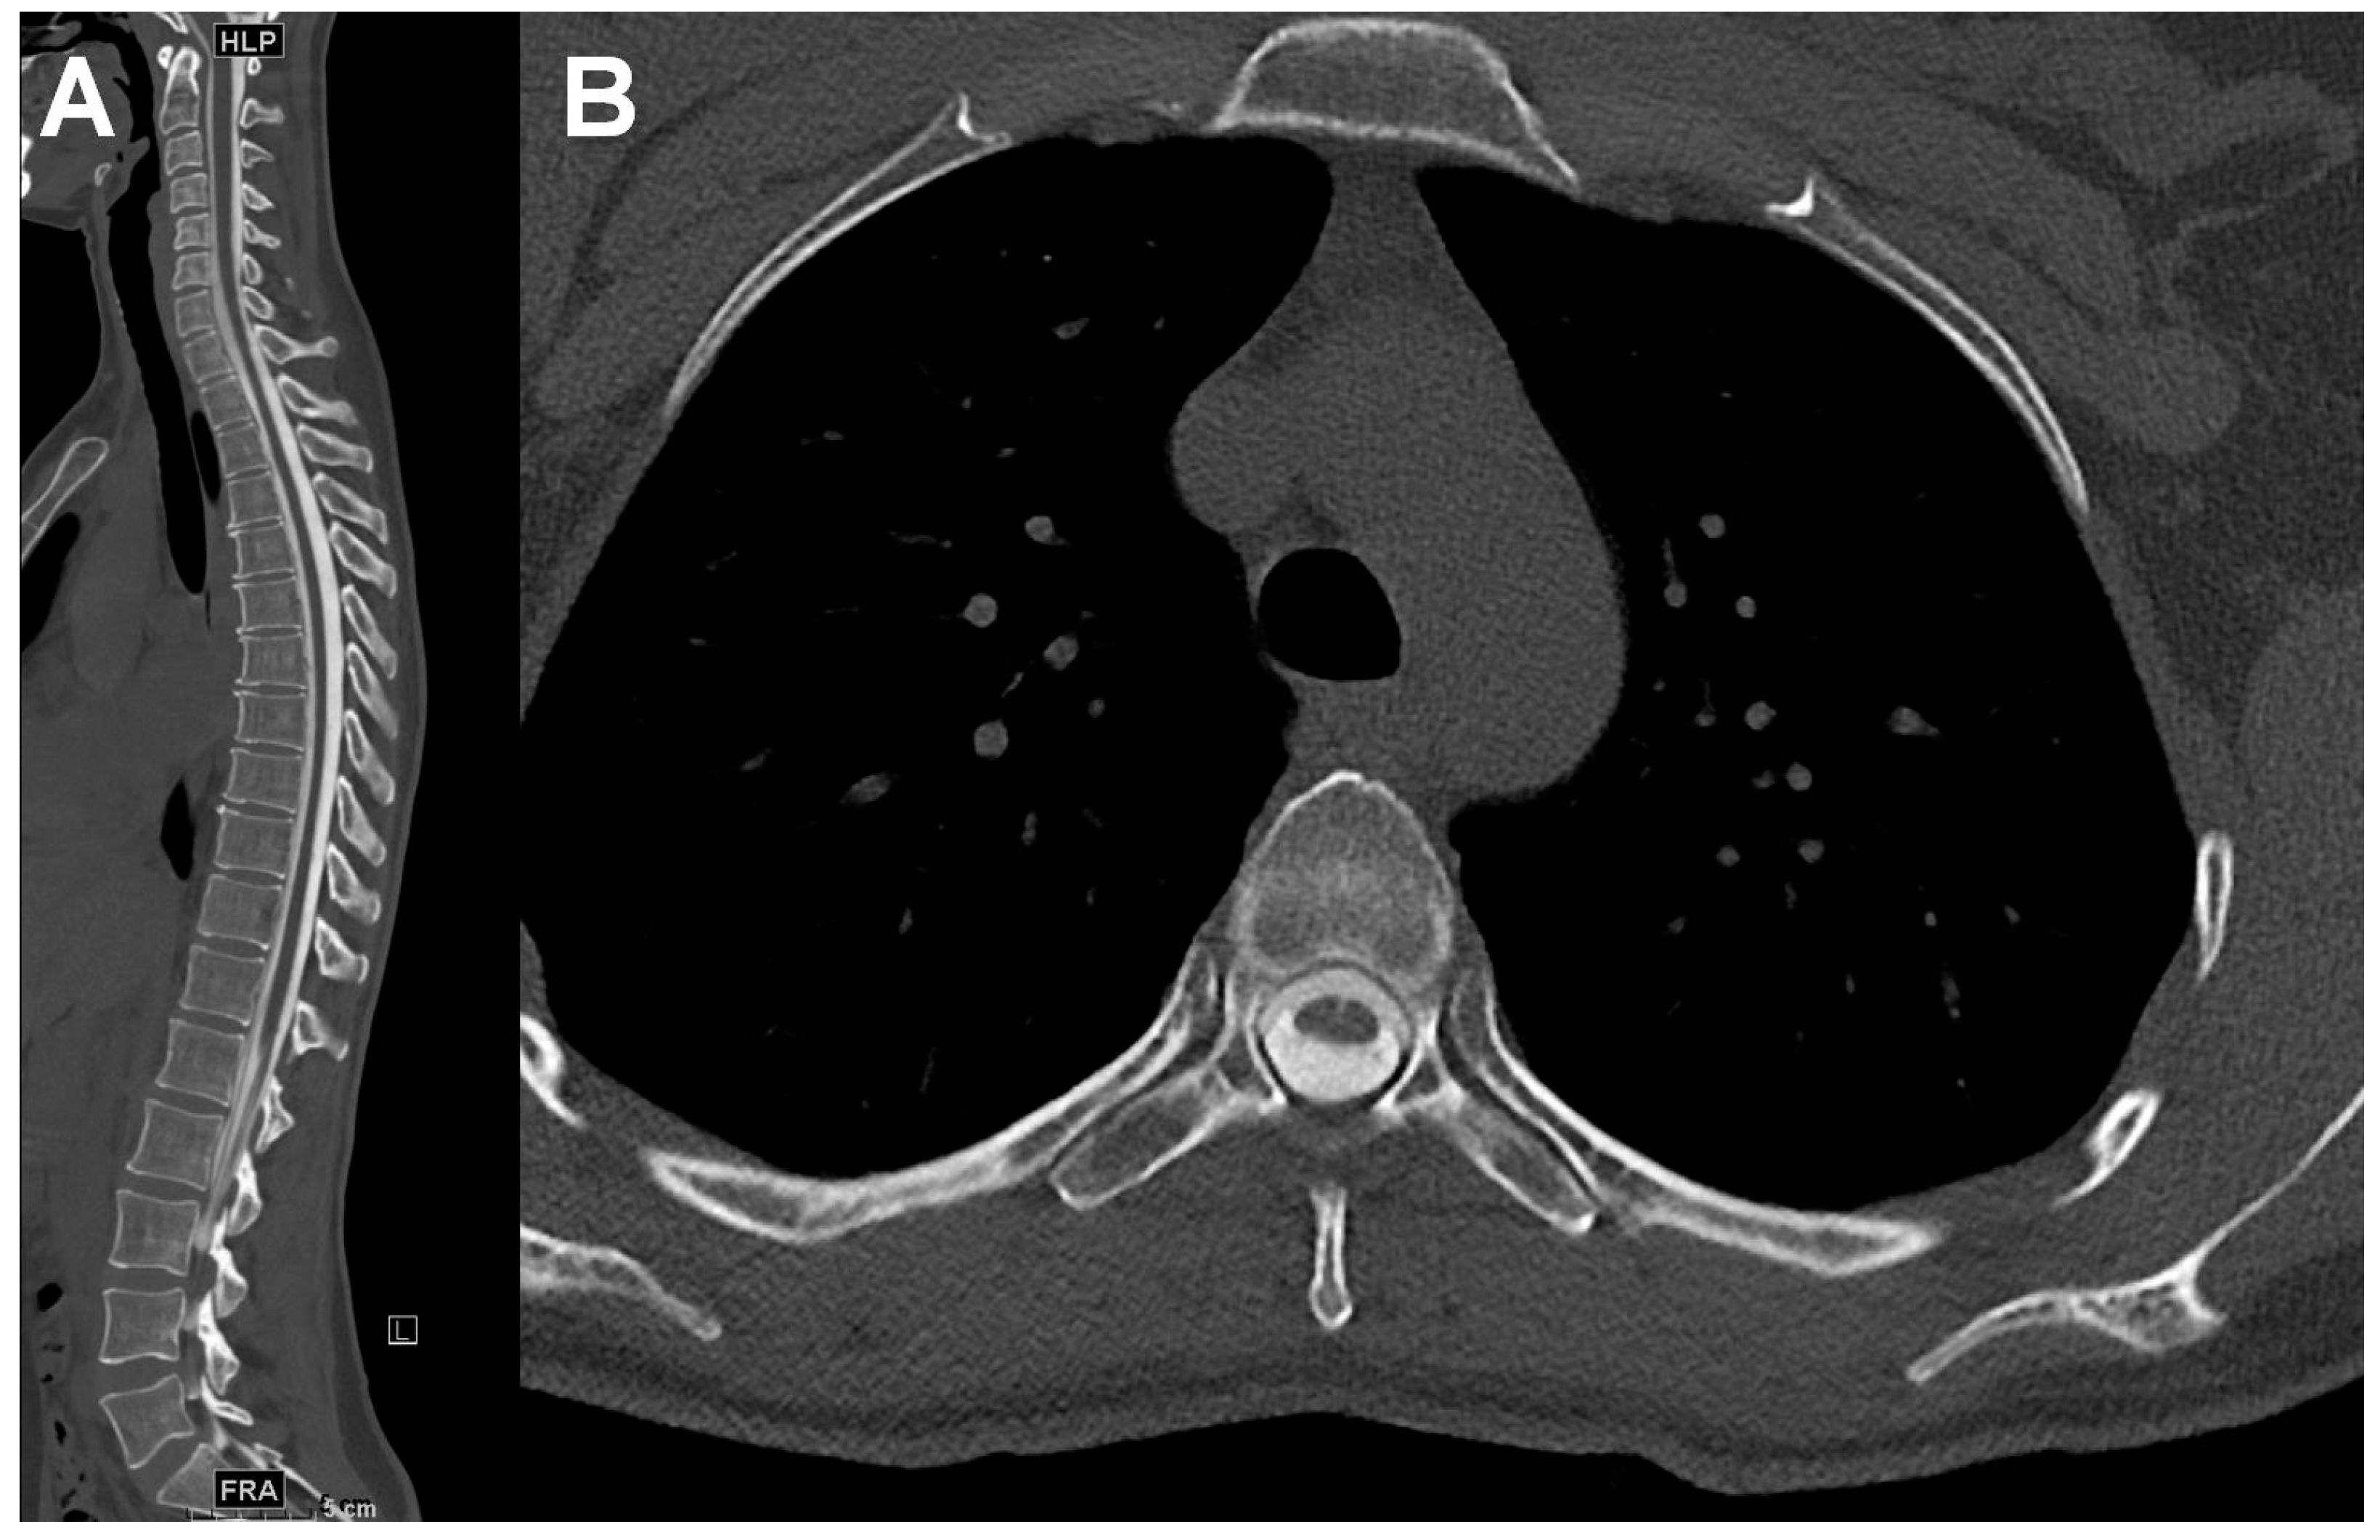

2.2. CT Myelography and CT Scanners